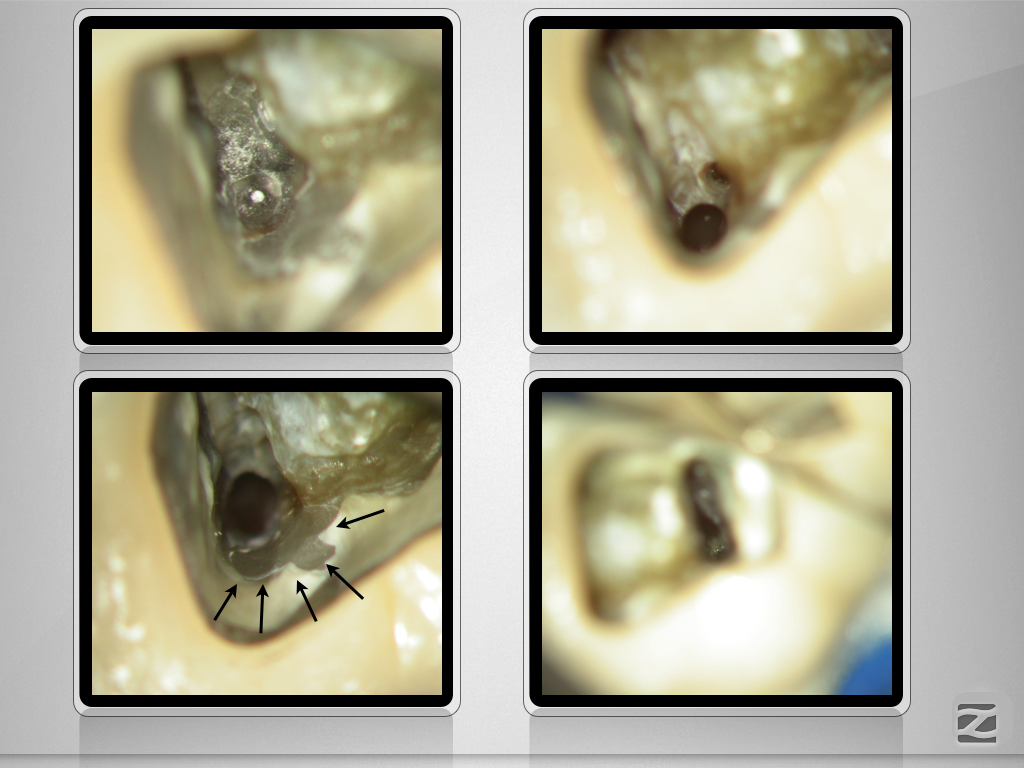

46D.002

Licht und Schatten …